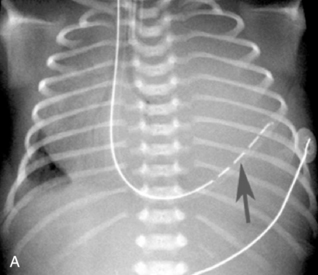

Atelectasis produces intrapulmonary opacification as the result of collapse of a portion of the lung tissue (Fig. 10-16). Atelectasis is usually seen as a diffuse increase in density with either a linear, angular, or streaked appearance in the affected area. Atelectasis is typically produced by intrinsic obstruction of an airway (caused by a mucous plug, exudate, or foreign body), extrinsic compression of the airway by another thoracic structure (e.g., enlarged lymph nodes, large heart, tumor), or significant hypoventilation. Because atelectasis represents loss of lung volume (i.e., lung collapse), other intrathoracic structures shift toward the area of atelectasis. The trachea, mediastinum, hilum, and any visible intrapulmonary septa can all shift toward the atelectatic area. If the upper lobe is involved, the loss of volume also elevates the hilum on the affected side. In addition, the hemidiaphragm on the involved side is elevated, and the intercostal spaces on that side become narrow. Air bronchograms may be present within the opacified area, and the visualized bronchi often are crowded together because of lung collapse. The uninvolved lung can become hyperinflated, producing a widening of the intercostal spaces on the nonatelectatic side and subsequent flattening of the hemidiaphragm.

image

Fig. 10-16 Atelectasis. Note opacification of the right upper lobe (small white arrow) and complete opacification of the left lung. Because atelectasis represents pulmonary collapse with associated volume loss, other structures have shifted toward the involved areas. The right hemidiaphragm is elevated, the hilum of the right lung is shifted upward, and the mediastinum is shifted to the left. Note the tracheal tube tip at the level of the third rib (large black arrow). The nasogastric tube ends in the stomach (small black arrow), with decompression of the gastric air bubble.